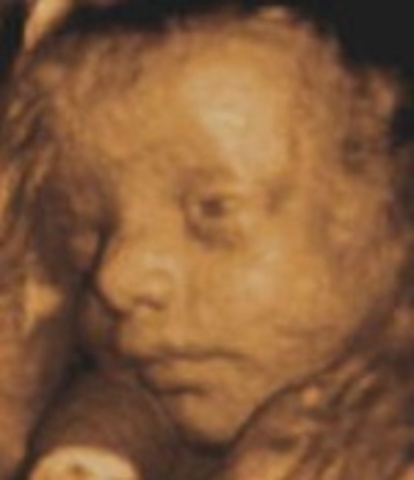

The baby is about 14 inches long and weighs over 1.7 pounds. At this time the baby's hands become quite active, and their eyes beguin to open.

The baby's brain continues to rapidly grow, and their eyes are able to open and close. At this time the baby weighs almost 2 pounds and is around 14.5 inches in size.